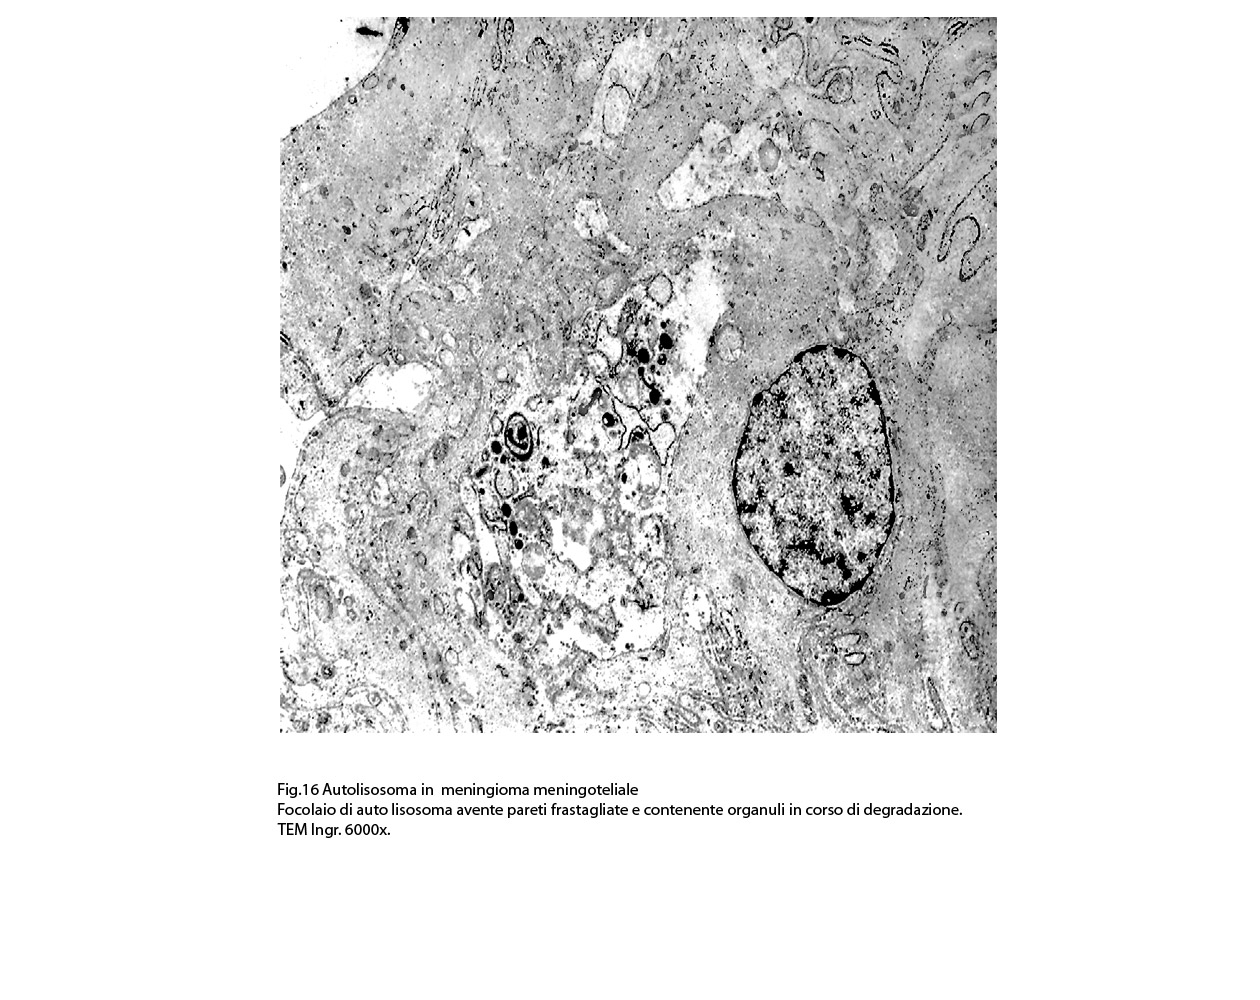

2/b AUTOLISOSOMA

Alcune cellule meningoteliali sono sedi, sopratutto a livello delle fasce periferiche, di ampie vescicole, di forma irregolare le quali sono demarcate da una membrana a mono-strato; gli spazi di queste vescicole sono in buona parte occupati da materiale amorfo, da frammenti filamentosi e da organuli intracitoplasmatici,tutto sottoposto a degradazione.

E’ possibile anche il reperto di elementi cellulari aventi il citoplasma occupato da ampie vescicole,delimitate da una membrana a monostrato, le quali sono ricolme di materiale amorfo,da strutture granulo-filamentose o da frammenti di organuli.

Non è raro il riscontro di cellule meningoteliali le quali hanno il citoplasma in buona parte occupato da una formazione cava,irregolarmente rotondeggiante; questa è delimitata da una spessa membrana ed è occupata da frammenti di citoplasma e da singoli organuli,tutto in corso di degradazione.

Nel contesto di alcune cellule coese,tutte contenenti focolai di micro e macroautofagia,è possibile rintracciare una di esse la quale è occupata da una ampia vescicola,a pareti frastagliate e lacerate, quasi ricolma di organuli e materiale filamentoso. Il citosol di tutte queste cellule è iperchiaro e gli organuli ivi contenuti sono in numero esiguo e mostrano segni morfologici di necrobiosi.